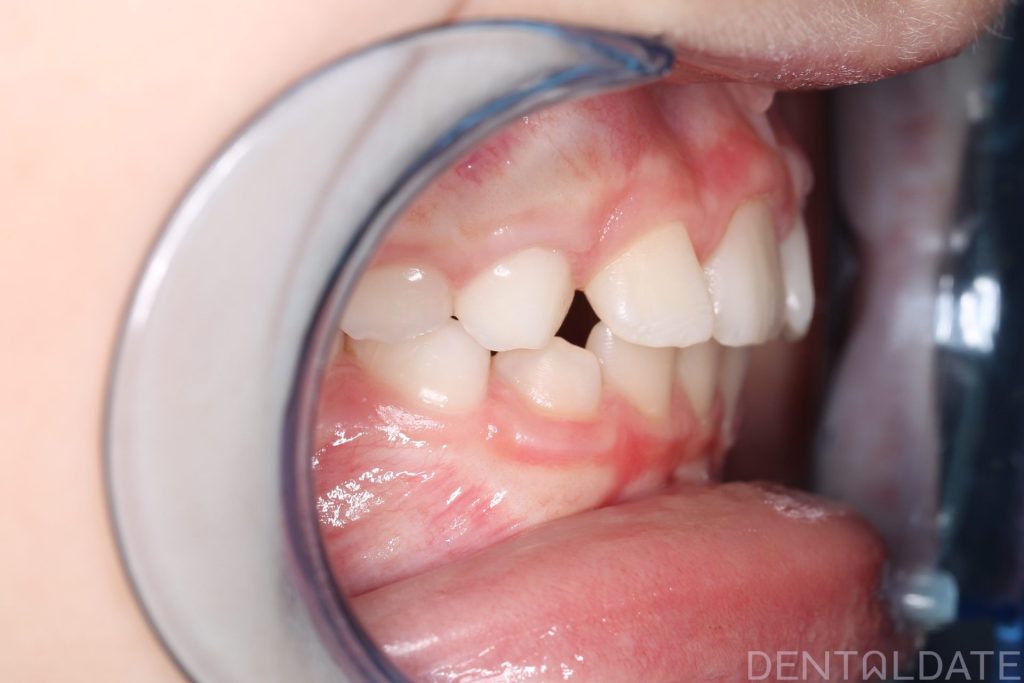

In this case, there was a severe lack of space for the permanent teeth, narrowing of the upper jaw, and the development of a malocclusion.

A Haas appliance was placed as the first stage of treatment, followed by the use of a myofunctional appliance.